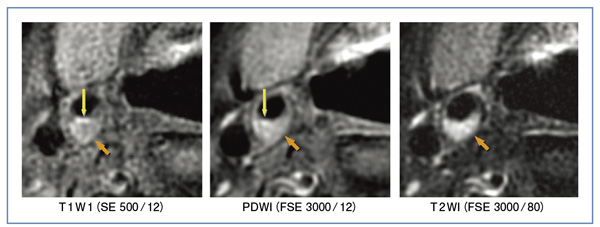

この標準化案に則って,日立メディコ社製1.5T MRI 「ECHELON Vega」にて撮像した画像を提示する(図2)。両側の内頸動脈にあるプラークが,明瞭に描出されていることがわかる。脂質主体のプラークで,T1強調画像で軽度高信号を呈しているが(←),潰瘍の部分は強い高信号を呈しており(↓),同部の血栓を描出していると考えられる。

われわれは最近,CEAの術前患者40例に標準化案MRプラークイメージングの撮像を行い,病理所見と比較した。ROC解析で求めたカットオフ値を用いると,T1強調画像では,出血成分とそれ以外とを鑑別する感度・特異度は89%・100%,脂質成分・出血成分と線維成分とを鑑別する感度・特異度は94%・100%と,きわめて良好な結果となった。従来の報告では,出血成分と他成分の識別感度・特異度は70〜84%・84〜97%,脂質・出血成分と線維成分の識別感度・特異度は85〜95%・75〜92%なので,それらと比べても優れた結果であると言える。また,T2強調画像では,脂質成分が高信号を呈する傾向があり,高い感度で他成分と識別可能であった。以上のことから,最適化された撮像条件であれば,T1強調画像を主体とし,T2強調画像を一部組み合わせることで,プラーク性状の正確な判定が可能であることが予想される。

図2 標準化案に則って撮像したMRプラークイメージング画像